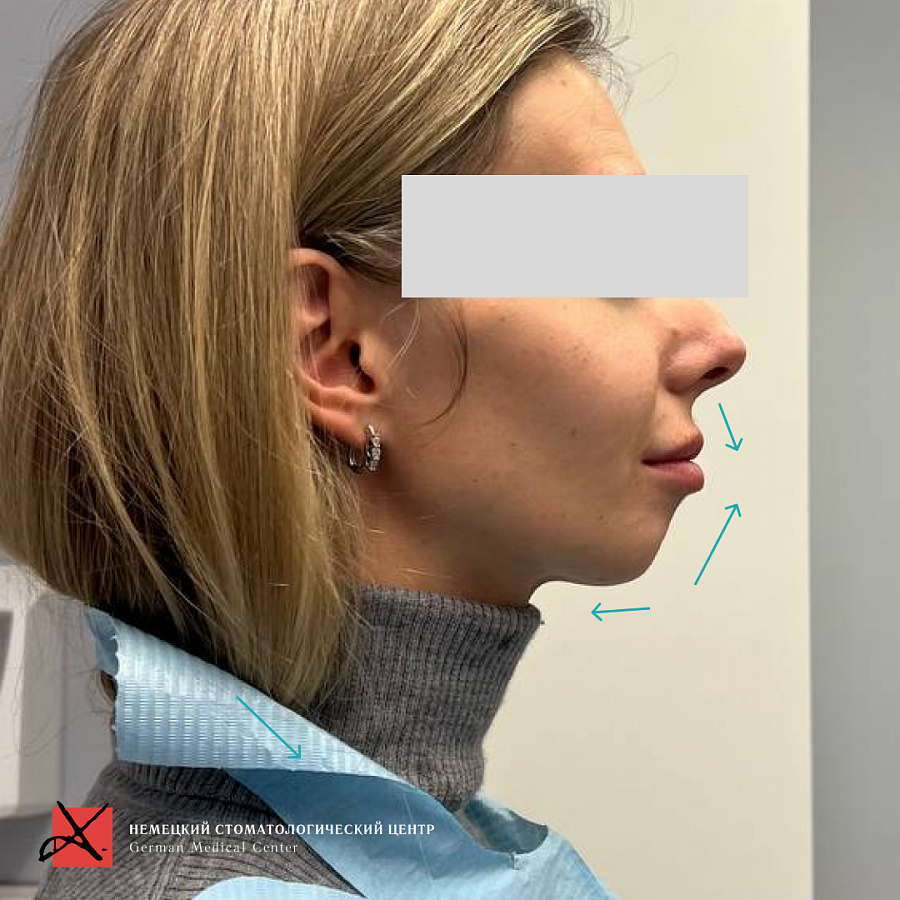

Пациентка пришла жалобами на неправильный прикус, который вместе с эстетическим дискомфортом и выраженной асимметрией лица доставлял ряд более серьезных проблем: головные боли, боли в шее и в суставах.

Основная проблема, с которой мы столкнулись - это отсутствие достаточного объема костной ткани для проведения качественной ортодонтии. Поэтому была выполнена частичная ортодонтия - перемещение зубов в имеющейся костной ткани в пределах возможного. Нижняя челюсть зафиксирована в нужном терапевтическом положении, комфортном для сустава. Далее было проведено ортопедическое лечение и реабилитация как боковых, так и передних отделов зубов.

В результате мы получили изменение контура лица, улучшение мимики мускулатуры лица, далее мы улучшили состояние сустава (он вообще перестал беспокоить!), шея расслабилась, благодаря чему ушли головные боли и боли от напряжения.

Также лечение привело к существенному изменениям внешнего вида пациентки.

В результате мы получили изменение контура лица, улучшение мимики мускулатуры лица, далее мы улучшили состояние сустава (он вообще перестал беспокоить!), шея расслабилась, благодаря чему ушли головные боли и боли от напряжения.

Также лечение привело к существенному изменениям внешнего вида пациентки.